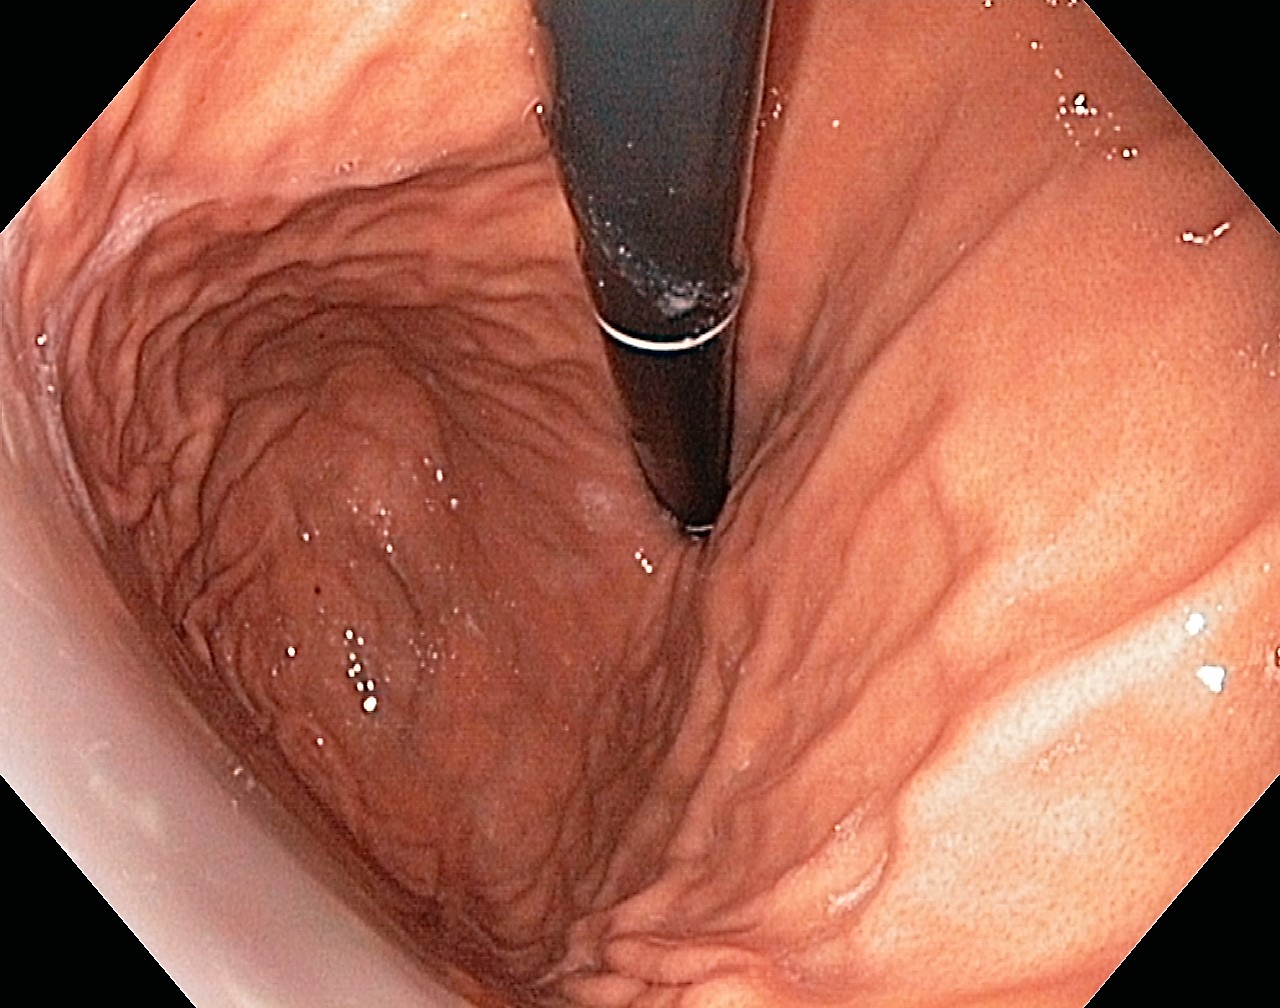

A Normal Gastric Fundus

A normal gastric fundus. Just click on a picture!